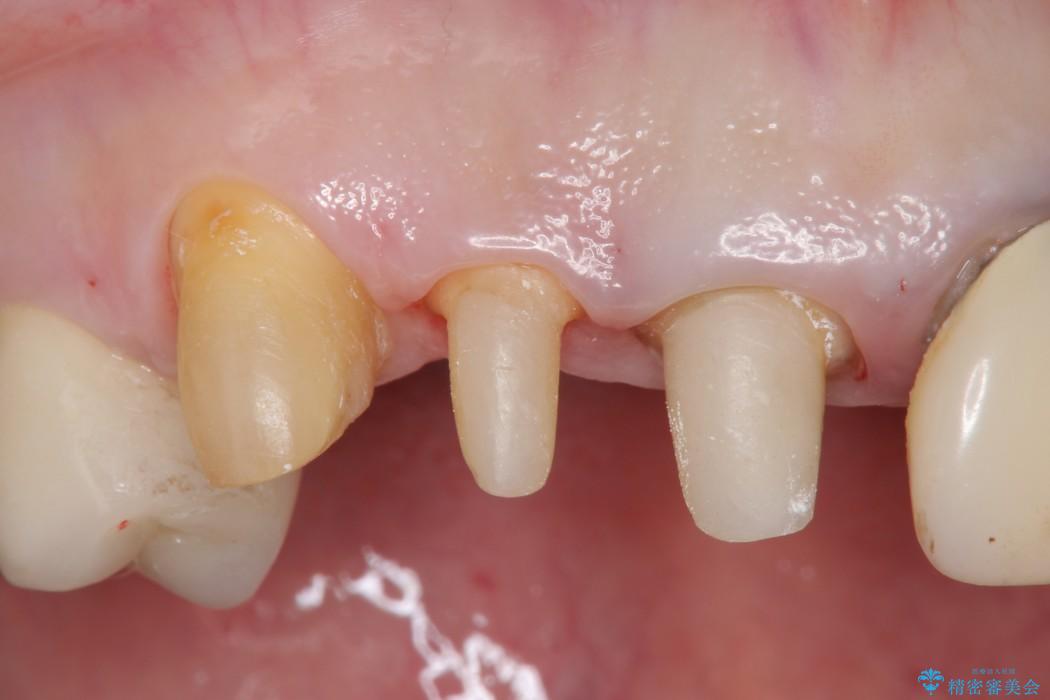

上顎右側の前歯2本のかぶせ物部分の再治療と犬歯に発生していた虫歯治療を主訴に来院されました。

前歯のかぶせ物に関しましては、内面が金属で覆われているため歯茎にその色が透けて見えるという審美的な問題と、かぶせ物と歯の境界が不適合であるという問題がありました。

犬歯の虫歯につきましては、何度も詰め物治療が繰り返されている痕跡があり今回虫歯を取りきるにあたり歯の強度に不安が残るため前歯と同時にかぶせ物の治療をしていくことを計画しました。

今回の症例では金属の色が透けていることを気にされていたので、土台から金属を除去し、金属を使用していないオールセラミックのかぶせ物を使用することとしました。